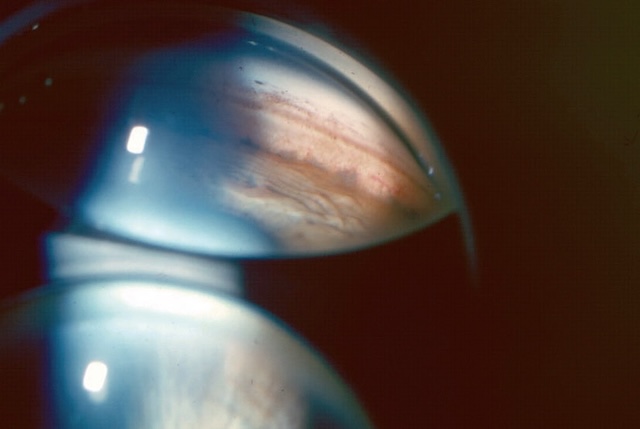

E 21Gonioscopie

On pratique parfois un examen de l’angle iridocornéen (fig. 1.33) ou gonioscopie, qui est réalisée à la lampe à fente à l’aide d’un verre de contact comportant un miroir permettant d’apprécier les différents éléments de l’angle iridocornéen (voir chapitre 14).

Cette photographie correspond à un examen en gonioscopie permettant de visualiser directement l’angle formé entre la cornée et l’iris, appelé angle iridocornéen. À travers le miroir utilisé pour cette technique, on observe un angle clairement ouvert, sans signe d’adhérences ni d’obstruction. Les structures comme le trabéculum apparaissent nettes, légèrement pigmentées, et la transition vers la sclère est visible. L’iris, quant à lui, présente une implantation régulière, sans bombement ni fermeture progressive. Ce type d’examen est essentiel dans l’évaluation du drainage de l’humeur aqueuse, notamment dans le suivi ou le dépistage des glaucomes.